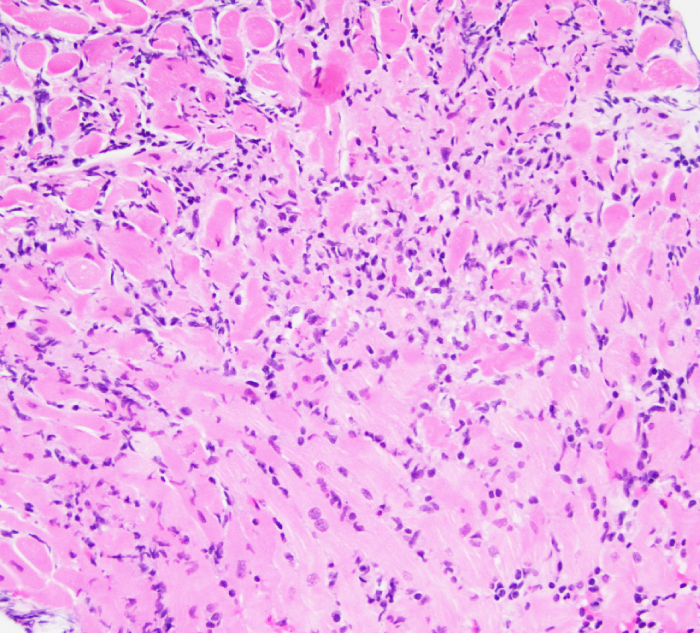

A 38-year-old man dies suddenly at his workplace and cannot be resuscitated.  He had experienced chest discomfort, shortness of breath, and fatigue in the week preceding the event.  The man was overweight but otherwise had no significant medical history.  He had no established primary care physician.  He did not use alcohol, tobacco, or illicit drugs.  Both parents are alive and healthy; a maternal uncle reportedly died of a heart attack at age 50.  Autopsy was performed and myocardial findings are shown in the slide below. A 38-year-old man dies suddenly at his workplace and cannot be resuscitated.  He had experienced chest discomfort, shortness of breath, and fatigue in the week preceding the event.  The man was overweight but otherwise had no significant medical history.  He had no established primary care physician.  He did not use alcohol, tobacco, or illicit drugs.  Both parents are alive and healthy; a maternal uncle reportedly died of a heart attack at age 50.  Autopsy was performed and myocardial findings are shown in the slide below.   Which of the following is the most likely diagnosis? A) Acute myocarditis B) Cardiac amyloidosis C) Congenital long QT syndrome D) Early-onset coronary artery disease E) Hypertrophic cardiomyopathy Which of the following is the most likely diagnosis?